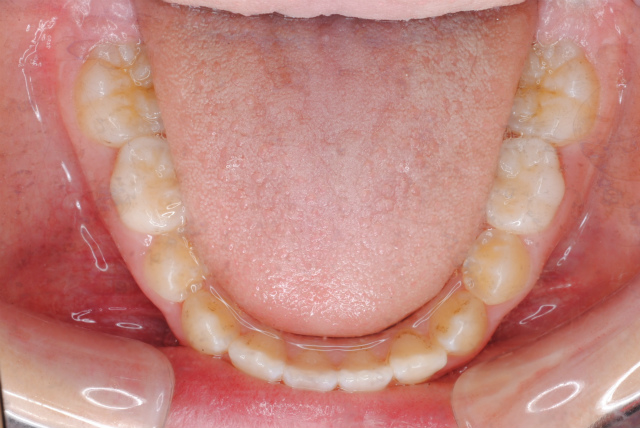

下の写真のように一見歯並びがきれいに並んでいて問題がないように見えますが、舌で前歯を常に押しているから歯並びが整っているに過ぎません。下顎歯列上に舌が覆いかぶさってしまっている様子がおわかりでしょうか。

現在 舌挙上のトレーニング中